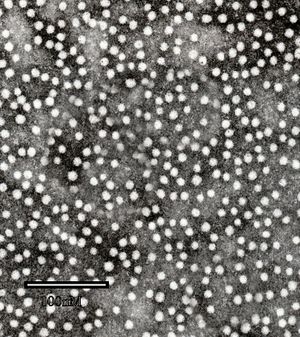

يتبع ڤيروس التهاب الكبد ب فصيلة الڤيروسات الكبدية.[9] جسيمات ڤيروس (الفيريون) تتكون من غلاف خارجي من المادة الدهنية ونيكلوكابسيد ايكوساهيدرال تتألف من البروتين. ويحتوى النيكلوكابسيد على الحمض النووي الڤيروسي وبوليميريز الحامض النووي الذي به نشاط عكس المنتسخة.[10] المغلف الخارجي يحتوي على البروتينات التي تعتبر جزءا لا يتجزأ من المشاركة في ملزمة الڤيروسية، ودخولها حيز، وخلايا حساسة. الڤيروس هو واحد من أصغر الڤيروسات الحيوانية التي يلفها الفيريون يبلغ قطرها من 42 نانومتر، ولكن توجد أشكال متعددة الأشكال، بما في ذلك الأجسام الخيطية والكروية التي تفتقر إلى جوهر. هذه الجسيمات غير معدية، وتتكون من الدهون والبروتينات التي تشكل جزءا من سطح الفيريون، وهو ما يسمى المضادات السطحية (HBsAg)، وتنتج في زيادة خلال دورة حياة الڤيروس.[11]

إن ڤيروس التهاب الكبد HBV) B) هو ڤيروس صغير مضاعف القشرة من فصيلة الڤيروسات الكبدية Hepadnaviridae. للڤيروس مجین DNA genome حلقي صغير ثنائي النطاق -double stranded جزئياً. يحتوي ڤيروس HBV عدة مكونات مستضدية هي والمستضد السطحي لالتهاب الكبد HBsA ) B)، والمستضد اللبي لالتهاب الكبد HBcAg) B)، والمستضد e لالتهاب الكبد HBeAg) B). يعتبر الإنسان المضيف الوحيد المعروف لڤيروس HBV، لكن يمكن لبعض الرئيسيات غير الإنسانية أن تصاب بالإنتان في الشروط المخبرية. إن HBV مرن نسبياً، وقد لوحظ في بعض الحالات بقاء الڤيروس معدياً على السطوح البيئية مدة شهر على الأقل في حرارة الغرفة.

هناك عدة أنظمة (مستضد - ضد) معروفة جيداً مرافقة لإنتان HBV. إن HBsAg والذي دعي سابقاً المستضد الأسترالي أو المستضد المرافق لالتهاب الكبد B هو محدد مستضدي determinant موجود على سطح الڤيروس وهو يتألف أيضأ من جزيئات تحت ڤيروسية subviral كروية وأنبوبية بقياس 22 نانومتر. يمكن كشف HBsAg في المصل بعد 30-60 يوماً من التعرض لڤيروس HBV، ويستمر لفترات مختلفة. إن HbsAg ليس معديا ، وإن الڤيروس الكامل (جزيء دان) هو المعدي فقط. ومع ذلك عندما يكون Hbs Ag موجوداً في الدم، فإن الڤيروس بكامله يكون موجوداً أيضاً، ويمكن للشخص أن ينقل الڤيروس. ينتج الڤيروس HBV كميات كبيرة من HbsAg أثناء عملية النسخ replication. إن المستضد اللبي HBcAg هو اللب البروتيني النووي المحفظي لڤيروس HBV، وهو غير قابل للكشف في المصل بالتقنيات التقليدية، لكن يمكن كشفه في نسيج كبد الأشخاص المصابين بإنتان HBV الحاد أو المزمن. أما المستضد (HBeAg) فهو بروتين ذواب موجود أيضاً في لب ڤيروس HBV، وكشف في مصل الأشخاص الذين لديهم عيارات عالية من الڤيروس، ويشير للعدوى (الإخماج Infectivity) الشديدة.

المضاد السطحي لالتهاب الكبد ب (HBsAg) هو الأكثر استخداما للكشف عن وجود هذا المرض. وهذا هو أول مضاد ڤيروسي يظهر خلال العدوى. ومع ذلك، في بداية الإصابة، قد لا يكون موجودا مضاد الڤيروس كما قد يكون غير مكتشف لاحقا من العدوى لأنها تتم إزالته من قبل المضيف. وتحتوى الفيريون المعدية على "الجسيمات الأساسية" داخلية التي تحتوى على الجينوم الڤيروسي. وتتكون الجسيمات الأساسية icosahedral من 180 أو 240 نسخة من البروتين الأساسي، والمعروف خيارياً باسم مضاد الالتهاب الكبدي البائي الأساسي، أو HBcAg. خلال هذه «النافذة» حيث لا يزال المضيف مصاب لكن يزيل الڤيروس بنجاح، والأجسام المضادة IgM لمضاد التهاب الكبد الوبائي ب الأساسي(anti-HBc IgM) قد يكون الدليل الوحيد المصلي للمرض.